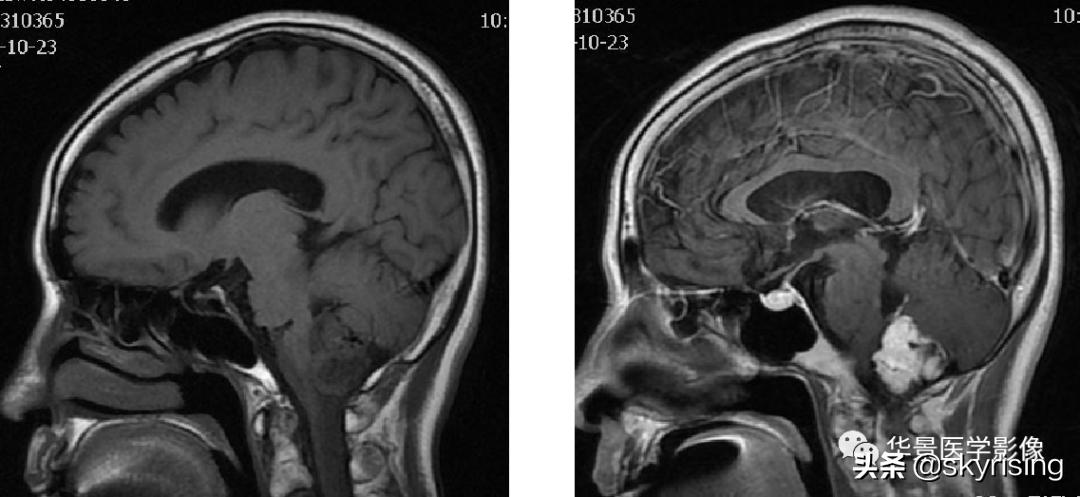

MR影像:

以下依次为T2WI、FLAIR、T1WI、增强、DWI及ADC:

上图白色箭头:小脑延髓池内延髓背侧不规则形团块影,延髓受压变形。

上图白色箭头:小脑延髓池内延髓背侧不规则形团块影,小脑半球、延髓、第四脑室受压变形,所见诸脑室未见增宽。

蓝色箭头:延髓受压前后径变窄,T1信号减低,考虑合并水肿。